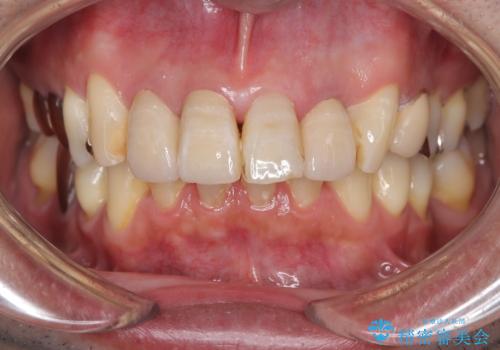

精密根管治療を行い、その後オールセラミッククラウンで審美的に修復しています。あわせてホワイトニングとエアフローによるクリーニングも行い、自然で美しい仕上がりとなりました。

他院で抜歯と診断された歯が、当院での治療により2本とも保存でき、見た目もきれいに仕上がりました。患者様にも大変ご満足いただけました。

抜歯と診断された場合でも、根管治療によって歯を残せることがあります。お気軽にご相談ください。